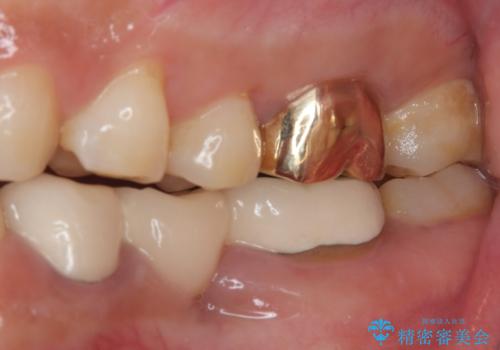

咬み合わせが非常に強く、臼歯のみに咬合力が集中している咬み合わせだったので、根管治療後はPGAクラウン(白金加金合金クラウン)にて補綴する治療計画となりました。

初回の根管治療を終えた2日後には膿の出口が消失し、咬んだときの不快な痛みもなくなりました。

PGAクラウンにしたことで咬み心地に全く違和感がなく、気にされていた審美面も、奥歯でありそれほど目立たないこともありますが、白金加金の色を気に入っていただけたので、患者様には大変満足していただけました。